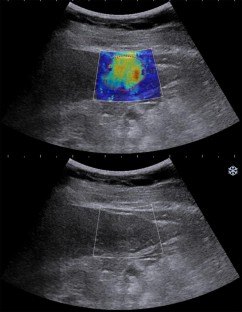

A total of 175 FLLs in 169 patients were prospectively analyzed. The study population was divided into a training cohort (n = 122) and a validation cohort (n = 53). The maxima, minima, mean, and standard deviation of 2D-SWE measurements were expressed in kilopascals (Emax, Emin, Emean, and ESD). The ultrasonics technique was used to extract the features from the 2D-SWE images. Support vector machine was used to establish two prediction models: the ultrasomics score (ultrasomics features only) and the combined score (SWE measurements and ultrasomics features). The diagnostic performance of the models in differentiating FLLs was analyzed.

Fig. 2